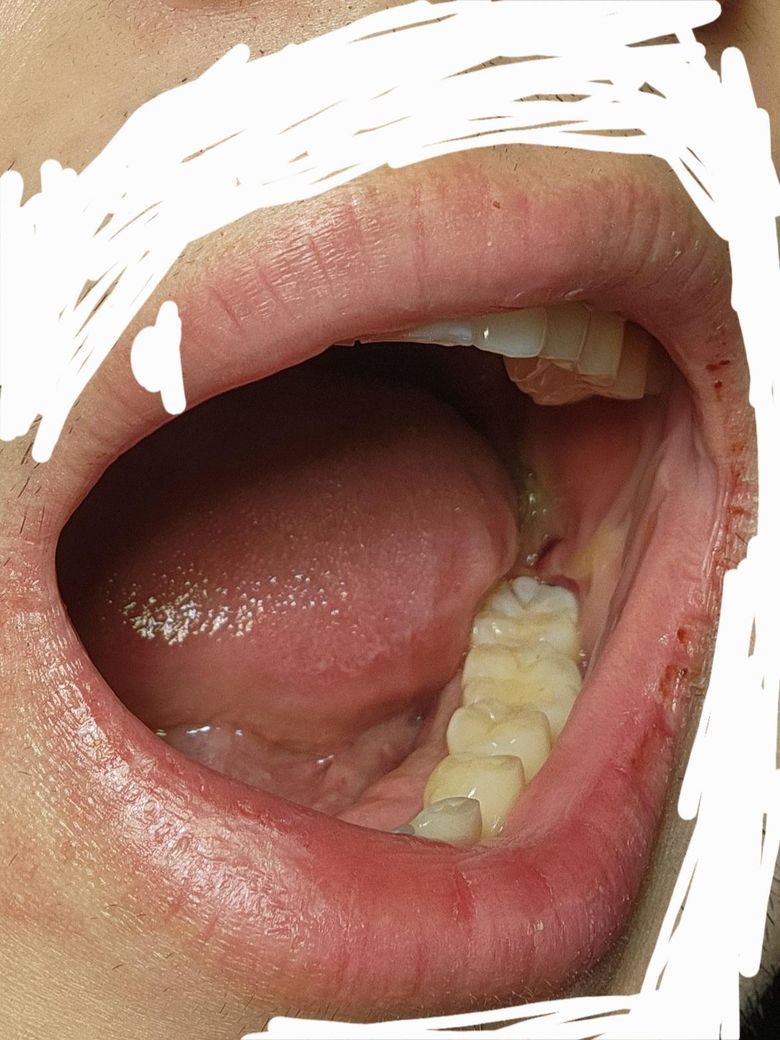

사랑니 발치 후 피떡이 떨어진거같은데 사진 정상인가요?

입을 헹굴때 너무 세게 행구지말라헸는데 그거를 지금 뽑고 3일 후에 알아서

그 동안 세게 행궈서 피떡이 떨어지진 않았나 너무 걱정되네요. ㅠㅠ

• 1번 째 사진

사진상으로 보면 지혈도 잘되고 잘 아물고 잇는거 같습니다. 자극만 가지 않도록 해주시면될것같습니다.

사진상 별 문제 없어보입니다 피떡은 원래 발치 후 1~2일이면 흡수됩니다 그 이상 남아있는 피는 피떡이 아니라 그냥 흘러나온 피고요 붓기는 사람에 따라 일주일까지도 갑니다

밑에 사랑니 뽑으시고 고생많으셨습니다 피떡은 구강 위해 환경을 차단해주는 보호막이라고 생각하시면 됩니다 그래서 피떡이 발치한 부위 위에 덮힐때까지 입을 너무 세게 헹구지 말라고 말씀드린겁니다 사진상 정확히 보이지는 않으나 큰 문제 없어 보입니다 붓기는 사람마다 다르나 보통 1주일 길면 2주일 정도 지속 될 수 있고 경우에 따라 붓기가 멍으로 바뀔수도 있으나 큰 문제 없으니 걱정 마시길 바랍니다 그 사이에 혹시 통증이 생기면 감염이 된거니 치과 방문하여 추가적인 약처방이 필요할 수 있습니다